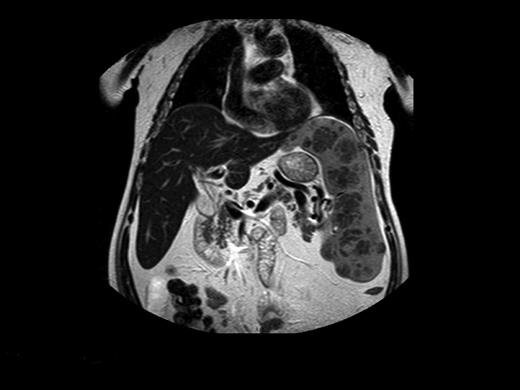

Before commercially available ERT in the 1990s, management of patients with GD was largely symptomatic. Beyond blood transfusions, iron supplementation, and treatment of infections, the important therapeutic modality was surgery. Total or partial splenectomy was the mainstay for massive splenomegaly or severe pancytopenia, but it is less needed since the advent of ERT. However, even with ERT, there are patients with massive splenomegaly and devastating parenchymal damage, including focal lesions, fibrosis, or ischemia, which may limit the organ's ability to respond to ERT (Figure 2).40 We have performed total splenectomies in very few such patients who failed to improve despite years of ERT (including high-dose regimens), specifically, unchanged thrombocytopenia or splenic volume. Dramatic improvement after splenectomy has several features: immediate normalization of platelet counts; decreased fatigue and bleeding tendencies; amelioration of the mechanical component that induced early satiety, abdominal discomfort, and possibly exertional dyspnea; and, for young women, freeing the abdominal cavity for an expanding uterus during pregnancies. I therefore consider the option of splenectomy for patients with huge splenomegaly who are unresponsive to therapy. ERT should be continued after splenectomy to protect against skeletal damage and hepatic complications, although this cannot be guaranteed. Splenectomy today (even for huge organs) may be performed laparoscopically, with improved postoperative recovery,41 a procedure that has been performed successfully in 3 of our patients with massive splenomegaly.

Magnetic resonance image of a 72-year-old man who did not respond to long-term high-dose ERT and improved after splenectomy. Courtesy of Dr George Blinder, Mar-Mor, Jerusalem, Israel.